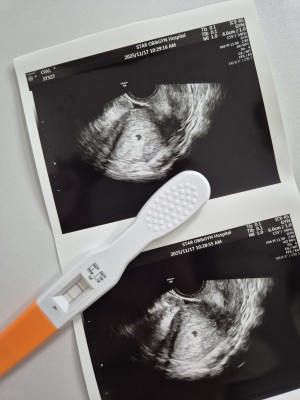

귀여운 아기집❤️

닉네임_I**********…

2025-05-15